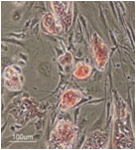

1. Mebiol® Gel中培养原发性肿瘤细胞

选取人肿瘤组织中的原发性肿瘤细胞进行培养该技术能够鉴定来自患者的原发性肿瘤细胞的表征,因此可根据其主要细胞化学敏感性,恶性肿瘤,转移酶活性和其 它参数对患者的治疗进行评估。在胶原或者3D凝胶中培养原发性肿瘤细胞,纤维细胞的过度生长可能对其产生抑制作用。而成纤维细胞在Mebiol® Gel中不容易增殖,因此能选择性增殖原代肿瘤细胞,以便后续进一步分析鉴别。

图 1:人体癌变结肠组织Mebiol® Gel培养10天。

(提供者:Dr. S. Kubota, Dept. of General Surgery, St.Marianna University School of Medicine)

人结肠癌组织在Mebiol® Gel培养10天。只有原发性肿瘤细胞中Mebiol® Gel中增殖。成纤维细胞在Mebiol® Gel中生长受到抑制,而在胶原蛋白和其它许多3D凝胶培养基质中,长满成纤维细胞,阻止癌细胞的增殖。